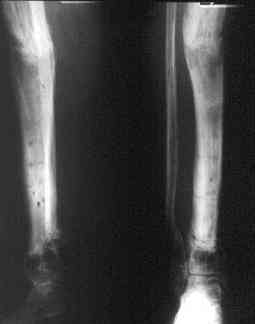

Может, данное наблюдение поможет в принятии решений в подобных ситуациях.

Огнестрельный дефект костей и передней группы мышц, поступил с юнилатеральным аппаратом, стабильность плохая, из раны обильное гнойное

отделяемое. #1;#2. Стержневой апп. снят, наложен апп. Илизарова, дренажно-ирригационная система промывки раны. #3; #4. После стихания инфекции,

аппаратом постепенно создана рекурвация для сближения контактов мышц (сухожилий) передней группы голени. #5;#6. Наложен шов на сухожлилия М.

Tibialis anterior и M extensor digitorum L. Одновременно компактотомия костей голени в В/3 для замешение дефекта костей. #7;#8. Постепенно

исправлена ось и возмещен дефект. В результате восстановление тыльной флекcии стопы и функции конечности. #9;#10;#11